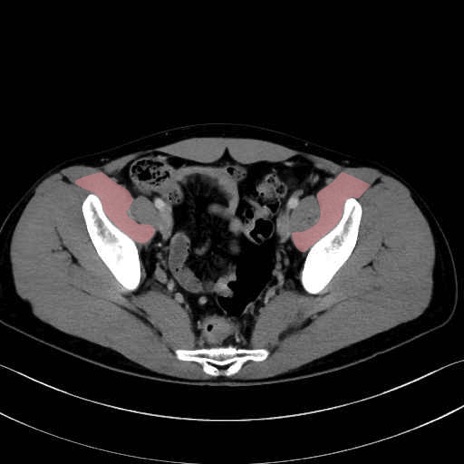

内閉鎖筋 (Obturator internus)